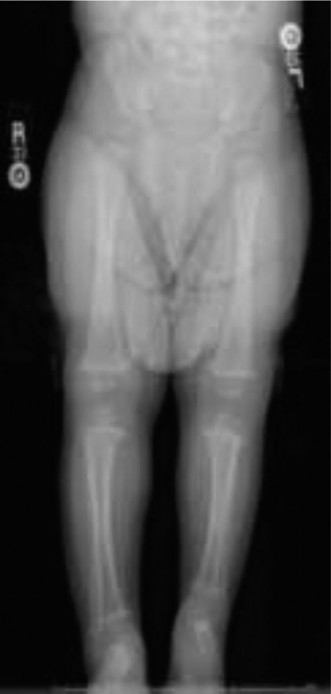

In the absence of its fibular counter-support, the tibia typically develops an anterior-medial procurvatum and varus deformity. This bowing can vary from subtle curvature to severe angulation, which may compromise overlying skin integrity or predispose to pseudoarthrosis. The inherent growth potential of the tibia may also be intrinsically affected, contributing to the progressive LLD. The distal tibial physis often appears irregular or dysplastic, and its growth plate activity can be disproportionately diminished, further exacerbating the LLD and angular deformities with growth.

The culmination of these anatomical deviations results in profound biomechanical impairments:

The absence of the fibula shifts axial weight-bearing stresses predominantly through the tibia, which is already structurally compromised. This leads to abnormal and uneven stress distribution across the ankle and foot, potentially accelerating degenerative changes.

The combination of LLD, ankle instability, and foot deformities gives rise to a compensatory gait pattern, such as circumduction, steppage gait, or excessive toe-walking. This results in increased energy expenditure, poor balance, and often chronic pain.

Progressive Deformity:

Without surgical intervention, both LLD and angular deformities tend to worsen with skeletal growth due to continued unequal growth plate contributions, asymmetric muscle pull, and abnormal loading.